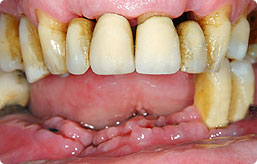

顾   客:李大伯 65岁

口腔情况:全口缺牙,多年不知肉滋味。

治疗方案:立得用种植牙体系

主诊医师:刘诚成医生